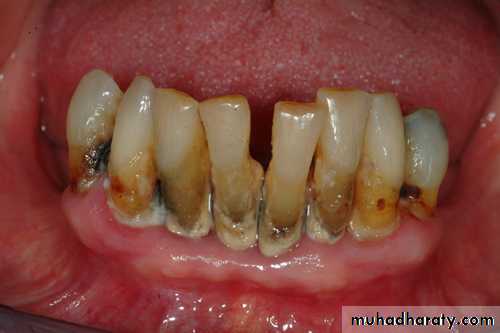

There are many indications for tooth extraction , if conservative treatment has either failed or is not indicated , a tooth May have to be extracted . The reasons for extraction of teeth are based on , the presence , function of the dentition as a whole and the patient`s attitude and education . Although the modern dentistry tries and takes all measures to preserve and maintain teeth in the oral cavity , but there are a variety of general indications for removing teeth :1- Severe caries :

This is the most common reason to remove a tooth. Badly carious teeth that are beyond restoration should be removed . Badly carious teeth result in deterioration of the oral hygiene resulted in bad oral hygiene and bad smell in addition to that sharp edges of the carious teeth leads to repeated ulceration to mucosa in addition to pain during eating and drinking . Untreated teeth with caries may end with pulpitis , periapical pathology etc…2- Server periodontal disease :